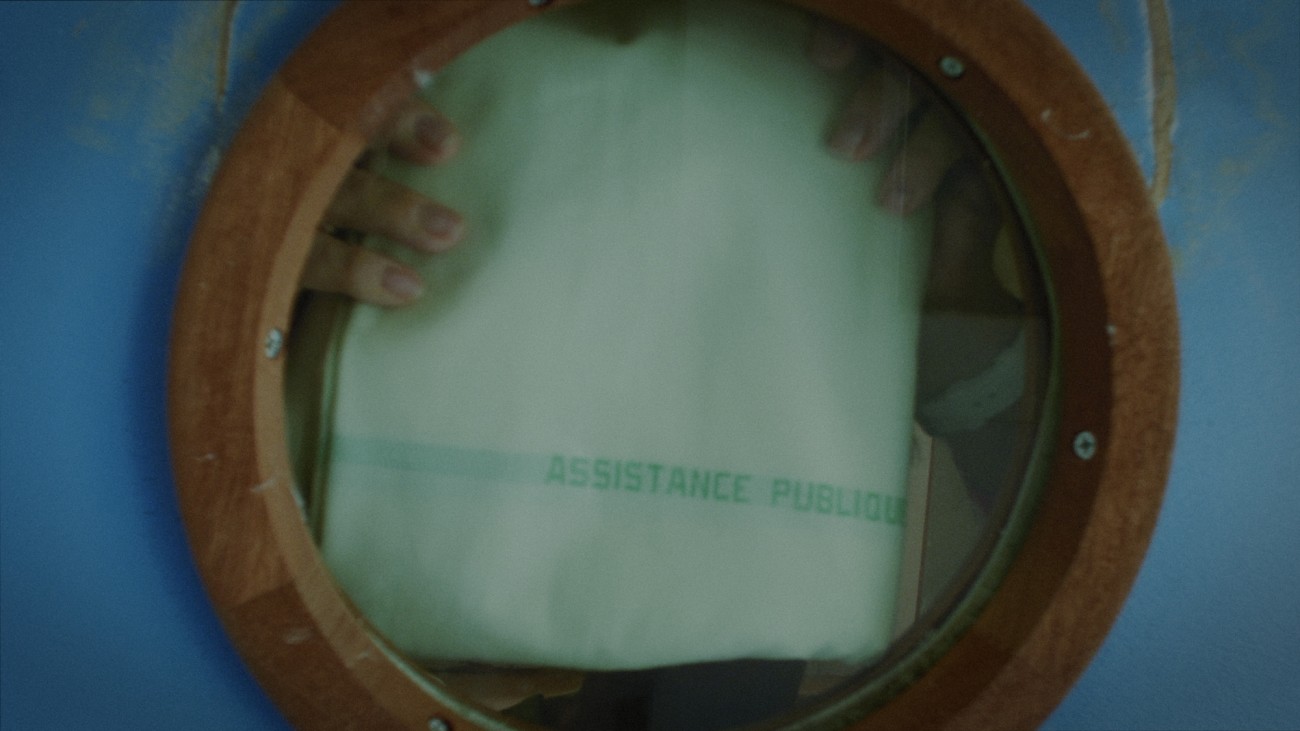

Reprenant le titre d’un traité d’anatomie du XVIe siècle, «De Humani Corporis Fabrica» s’intéresse à ce qui se passe non pas à l’intérieur de l’hôpital mais à l’intérieur des patients. Aux liens qui unissent le corps médical aux corps défaillants, fracassés, au bord de l’extinction. Il y a cinq siècles l’anatomiste André Vésale ouvrait pour la première fois le corps au regard de la science. «De Humani Corporis Fabrica» ouvre aujourd’hui le corps au cinéma. On y découvre que la chair humaine est un paysage inouï qui n'existe que grâce aux regards et aux attentions des autres. Les hôpitaux, lieux de soin et de souffrance, sont des laboratoires qui relient tous les corps du monde…